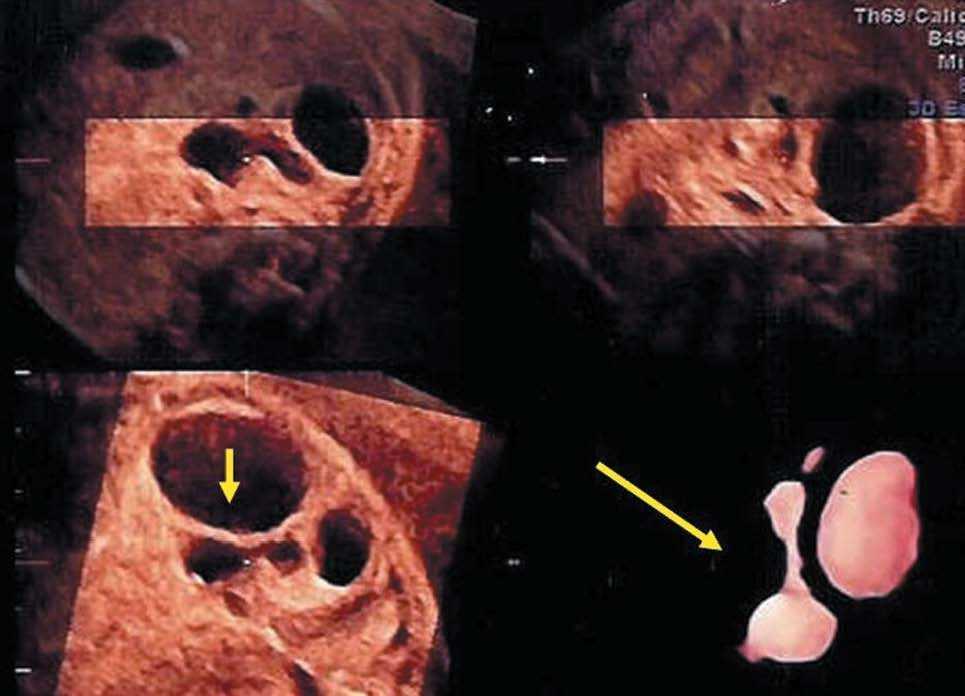

Se han aplicado recientemente para diagnosticar enfermedades fetales, especialmente combinando con el modo inverso, ya que así es posible visualizar las colecciones líquidas de cualquier etiología y observar su relación anatómica con los órganos adyacentes.

Se han realizado estudios4 sobre hidrocefalias, derrames pleurales (fig. 7), atresias duodenales y enfermedad renal (fig. 8).

Figura 7.El modo inverso muestra la dilatación bilateral de los ventrículos laterales. Un tercer ventrículo dilatado está presente con conexiones superiores hacia los ventrículos laterales a través del agujero de Monro. (Cedido gentilmente por W. Lee4.). Abajo se observa una colección pleural, y un hidrotórax que desplaza y comprime corazón. Se ven parcialmente 3 costillas y el corte del resto. El modo inverso muestra el área cardíaca desplazada y comprimida.

Figura 8. Poliquistosis renal (modo inverso). Se aprecian varios quistes e hidronefrosis marcada por la flecha amarilla.